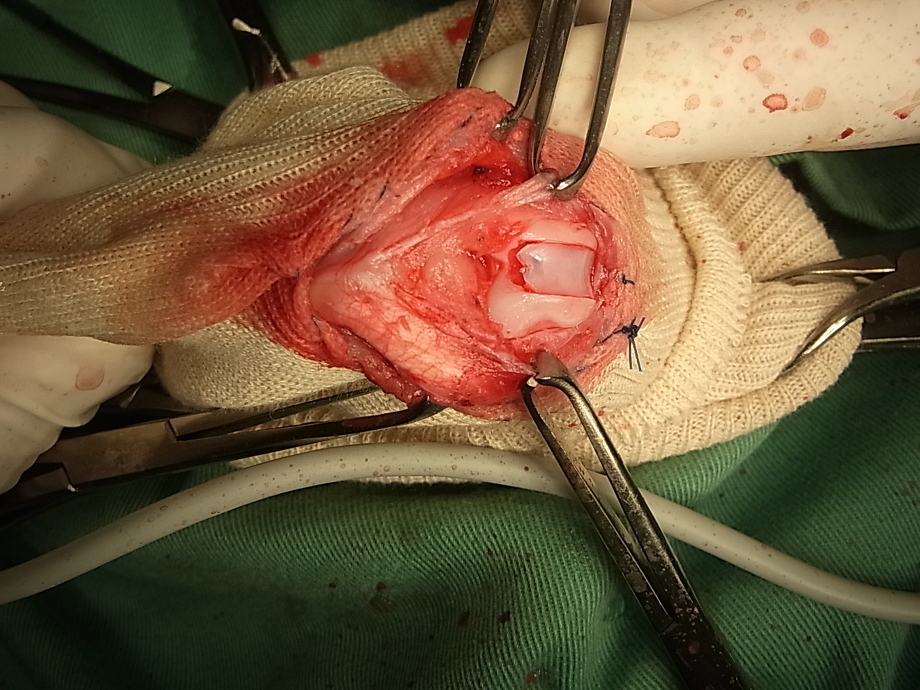

プードルに行った手術の写真です。程度としてはグレード2でした。これは膝蓋骨がすべるレールにあたる滑車溝を深くするために切れ目を入れています。

切れ目に沿って軟骨をブロック状に掘り出しています

掘り出したところです。

掘り出したブロック状の軟骨です。このあとブロックのあった部位を掘り下げそこにブロック状の軟骨をもどします。これにより軟骨を残した状態で溝を深くすることができます。軟骨を残さずに軟骨自体を削り取り深くする方法もあります。小型犬であれば問題ないとされています。